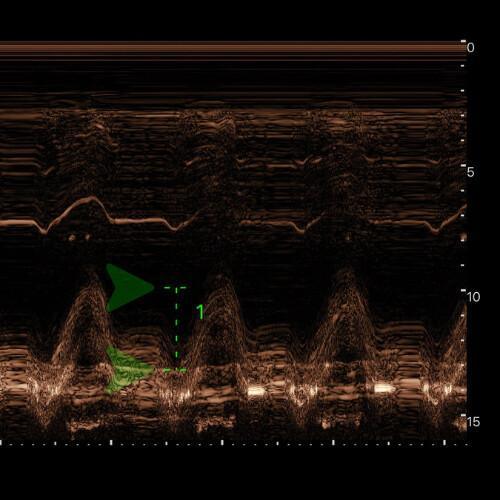

TAPSE (déplacement systolique de l’anneau tricuspide) : normal > 17 mm.

🖥 Vue : en A4C centrée sur le VD et l’anneau tricuspide latéral.

🎯 Alignement : le curseur en Mode M exactement sur l’anneau tricuspide latéral (jonction VD/oreillette droite, paroi libre).

📈 Lancement mode M : on active le mode M et on vérifie qu'il y a une courbe avec un mouvement net de va-et-vient de l’anneau (un pic systolique bien visible).

📏 Mesure : on mesure en millimètres la distance entre le point le plus bas en diastole et le point le plus haut en systole (amplitude du pic).

✅ Interprétation :

TAPSE ≥ 17 mm → fonction systolique du VD conservée

TAPSE 13-17 mm → dysfonction légère

TAPSE 10-13 mm → dysfonction modérée

TAPSE < 10 mm → dysfonction sévère

![]()